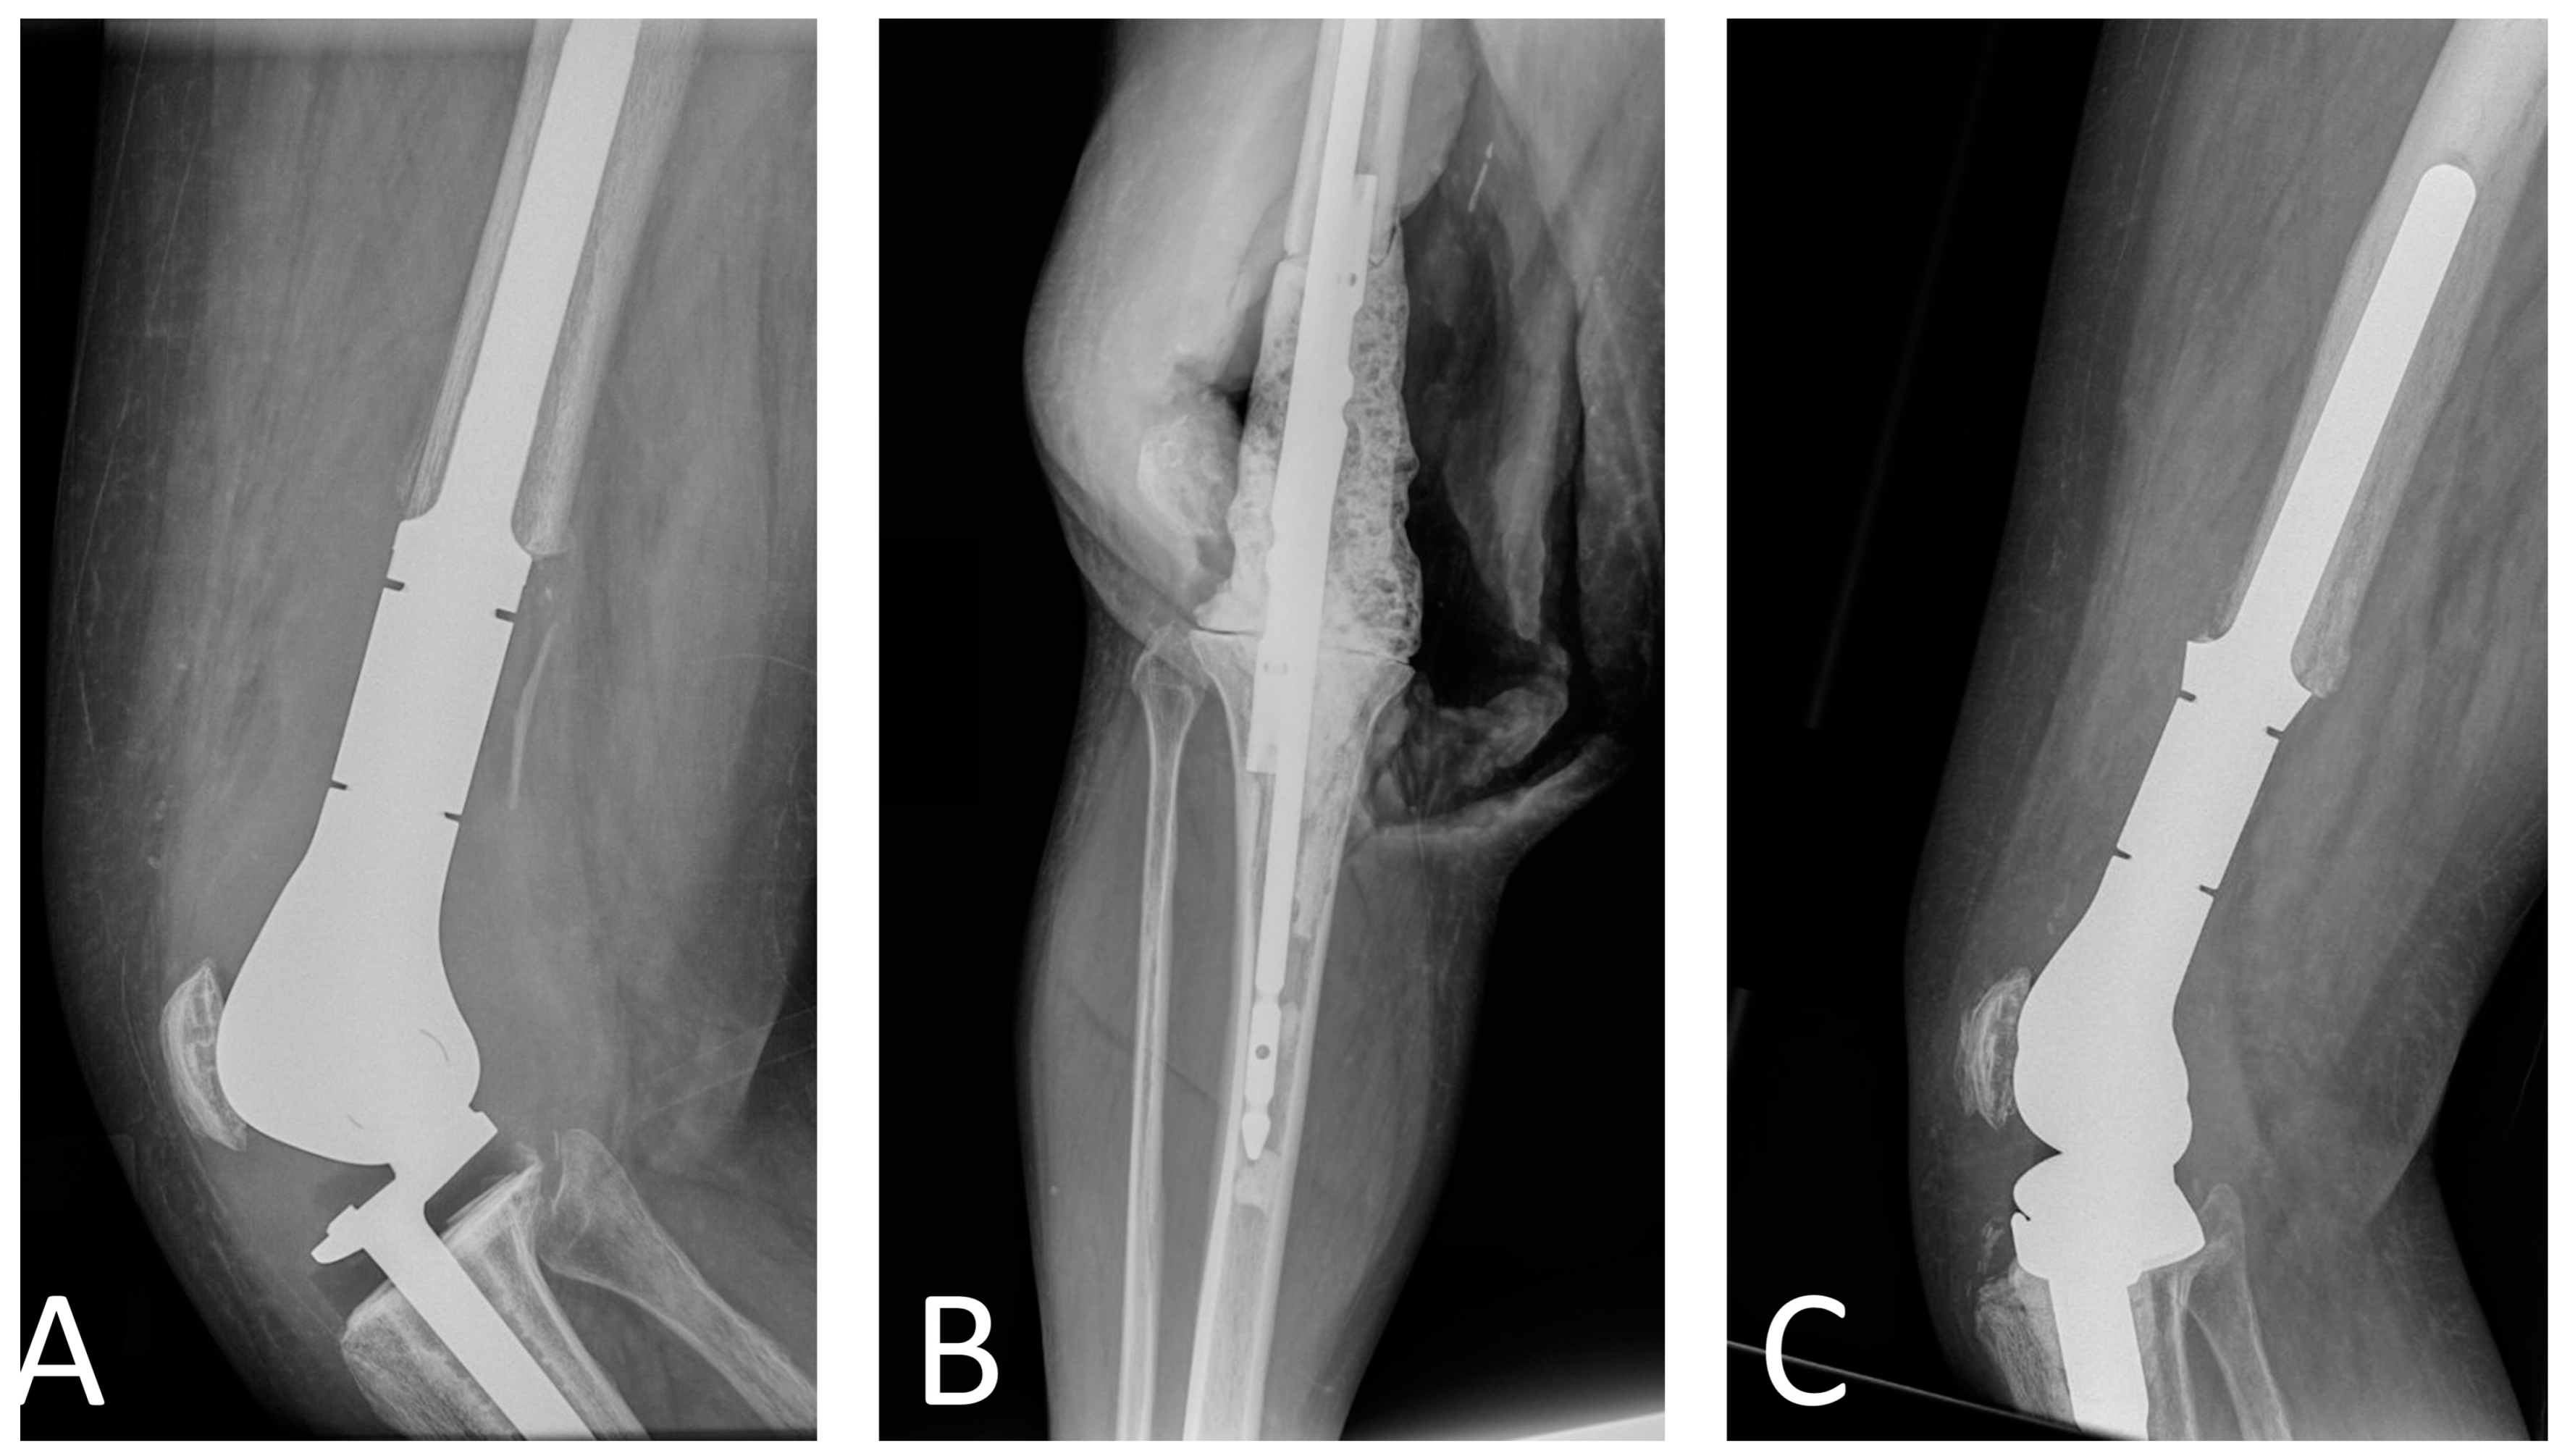

Two-stage revision is the gold standard for the management of megaprostheses PJI. This surgical strategy requires removal of all components, thorough soft tissue debridement, and placement of a cement spacer. Due to the morbidity of removing fixed components, some surgeons have advocated for a partial two-stage revision with stem retention, citing positive outcomes [37]. However, these findings stem from a single study that included 11 patients treated with this procedure and 4 patients with complete two-stage revision. In our opinion, retention of the stems does not allow for complete PJI eradication, and more recent data underscore this point [22]. Sigmund et al. analyzed the outcomes of 32 patients treated with two-stage revision for megaprostheses PJI and reported a 77% success rate for patients treated with complete stem removal and 36% for those with incomplete stem removal [22]. Regarding spacer construction for PJI involving megaprostheses around the knee, we recommend the use of two tibial nails, which serve as a scaffold for the antibiotic-loaded cement (Figure 1). Alternative spacer manufacturing techniques using Kuntscher nails and cement guns have been described [18]. Unless contraindicated, combination of 3 g of vancomycin and 3.6 g of tobramycin per 40 g package of bone cement is recommended [72]. Given the large size of these defects and the impossibility to use all cement bags with antibiotics, we recommend that the antibiotic cement is used at the bone–spacer interface and, secondarily, in the periphery of the spacer. A key feature in two-stage revisions is to ensure that a spacer of sufficient size is used to preserve the cavity in which the new prosthesis will be reimplanted in the second stage [18]. As patients with megaprostheses PJI often require higher doses of local antibiotics than those used in conventional PJI, surgeons should also be aware of the high risk of post-operative acute kidney injury (AKI) [77]. Underlying chronic kidney disease, high baseline creatinine, low preoperative hemoglobin, and blood transfusion requirement have been identified as risk factors for AKI after spacer insertion [78]. Although no specific time to reimplantation has been established, Jeys et al. recommended leaving the spacer in place for a minimum of six weeks [36]. Moreover, they recommended performing reimplantation only if no organism grew after three weeks of culture of periprosthetic aspirate. An antibiotic-free interval before joint aspiration (antibiotic holiday) of 2 weeks should be considered to minimize the number of false negative results [79].

Figure 1.

Radiographs of patient with distal femur replacement PJI treated with two-stage revision. (A) Pre-explantation radiographs, (B) intraoperative radiographs of the spacer with two tibial nails, and (C) post-reimplantation radiographs.